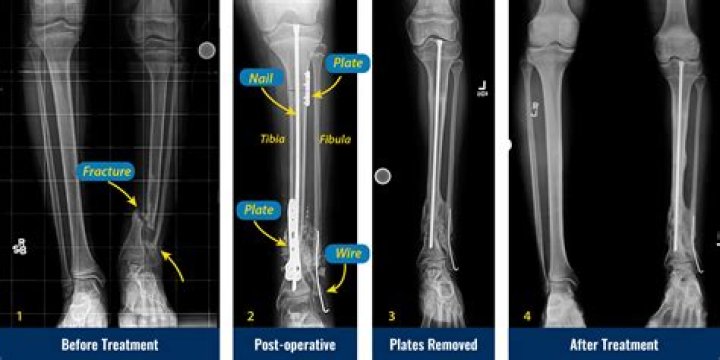

Congenital Pseudoarthrosis Treatment by Paley Cross Union Protocol

Congenital pseudarthrosis of the tibia is a shin bone fracture in children that has not healed. It normally presents before a child turns two years old.

Congenital pseudoarthrosis of the tibia describes abnormal bowing that can progress to a segment of bone loss simulating the appearance of a joint. The condition is usually apparent shortly after birth and is rarely diagnosed after the age of two.

What is tibial pseudarthrosis?

Tibial pseudarthrosis is the name given to a fracture of the tibia (the larger of the two bones in the lower leg) that does not heal correctly.